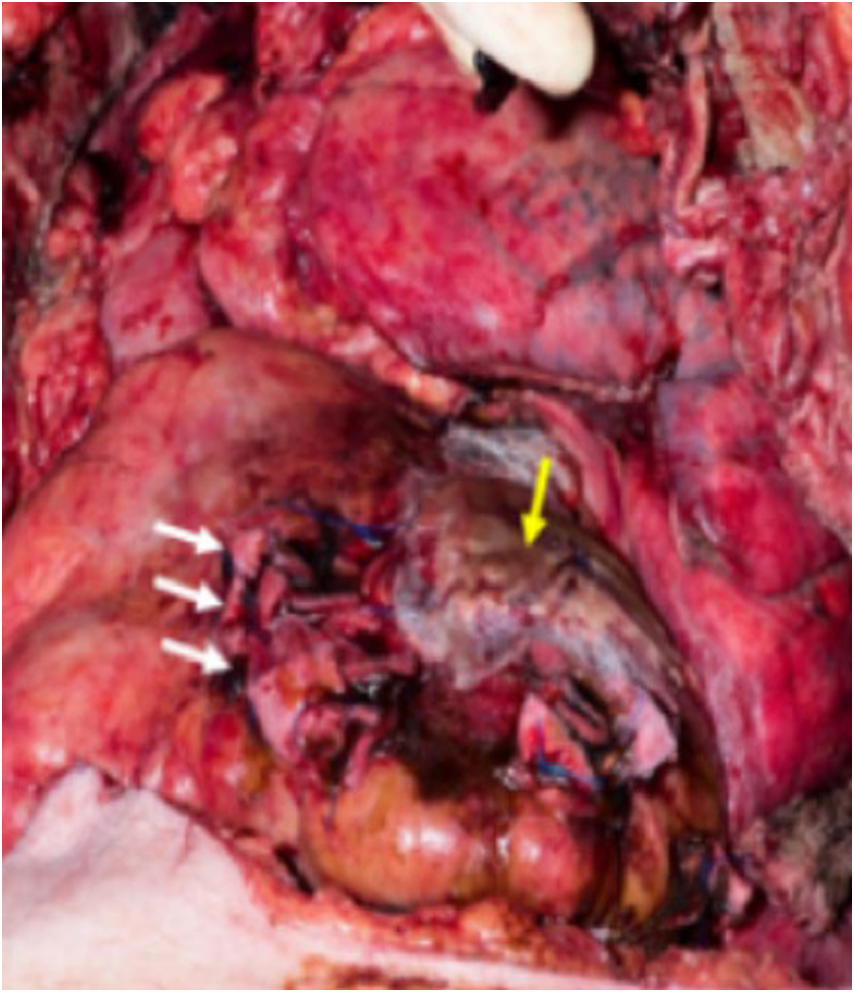

Opening the pericardium allowed immediate decompression of the tamponade. Following removal of the nails, quick inspection revealed seven myocardial lesions, some of them very close to the left anterior descending branch. Median sternotomy to improve exposure and allow better access to all injuries was performed: during that time, control of the most important myocardial injuries was performed with fingers and swabs. The lesions of the ventricular wall were closed using 2.0 polypropylene, while a diffuse epicardial venous bleeding was covered with a xeno-pericardial patch under which bio-glue (CryoLife Inc. GA, USA) was injected (Figure 4). Despite sufficient hemostasis within the chest, the patient remained unstable. Median laparotomy was performed to exclude intra-abdominal bleeding; this allowed removal of the last two nails that had perforated the stomach. These injuries were sutured with 4.0 Polydiaxone. The patient received 6 units of red blood cells.

Figure 4. Intraoperative picture during repair of the right ventricular lesions (white arrows) and pericardial patch covering the left ventricular lesion (yellow arrow).